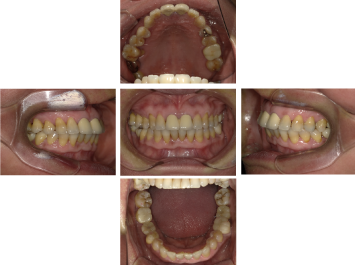

50代 インプラント治療(右上3左上3のみGBR)

| 年代・性別 | 50代・男性 |

| 主訴 | 入れ歯が合わず毎日ヨーグルトしか食べることができないので、しっかり咬めるインプラントにしたい。 |

| 部位 | 右下⑦⑥5④ 上顎③2①①2③ 左下67 |

| 治療期間 | 約9ヶ月 |

| 費用 | ¥4,273,500(税込) |

| 副作用・リスク |

|